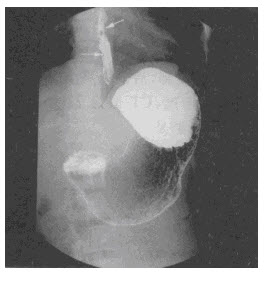

钡餐片子正常图片,

x线钡剂造影食管充盈缺损

患者,男,42岁.吞咽阻挡感6个月,食管钡餐见图.最可能的斩断是)

正常食管造影图片